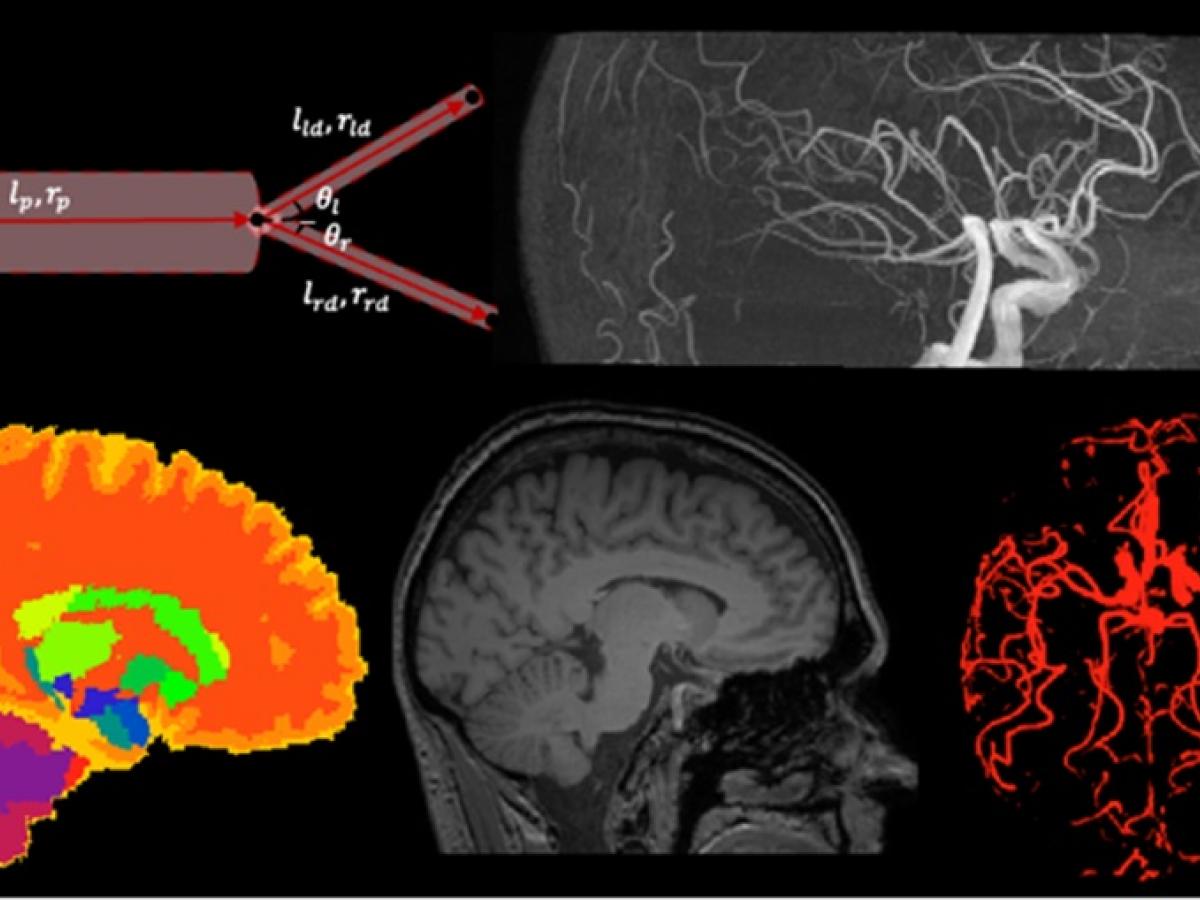

AIML Research Seminar: Anatomically Aware Brain MRI Segmentation of the Cerebral Vasculature

This presentation outlined Georgia's approach to synthetic data utilisation in network training, for cerebral vessel segmentation in brain MRI. She discussed the process of using unlabelled brain MRI and cerebral vasculature literature to produce a method that has the potential to not only enhance segmentation performance, but also reduce the need for large amounts of labelled, training data and improve model explainability and reliability, making networks more suitable for real-world clinical applications.